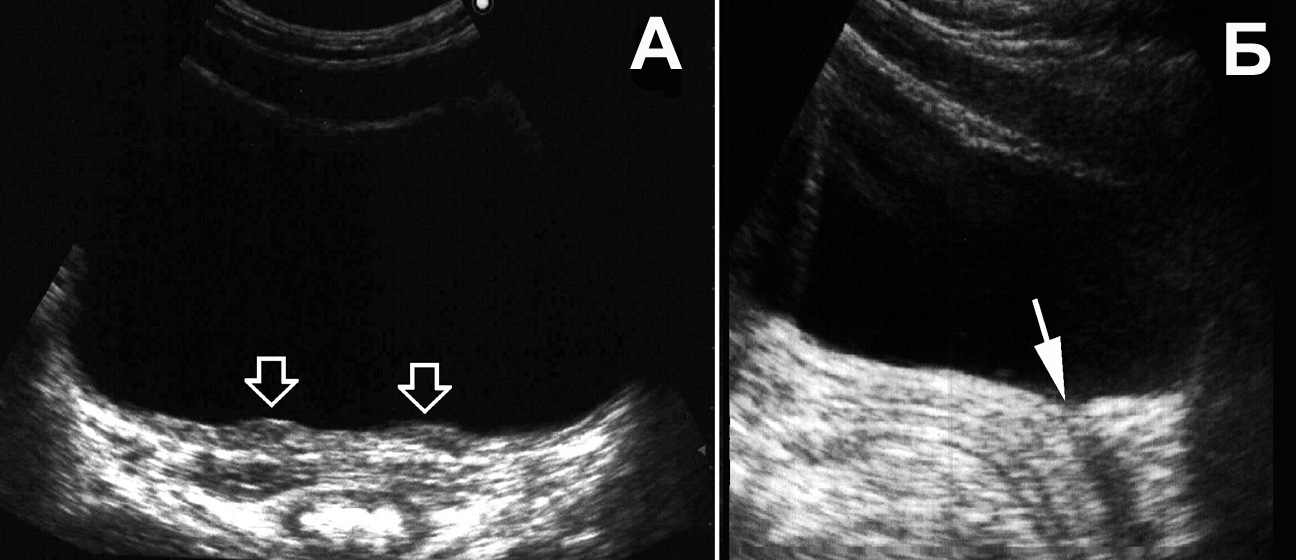

Рис. 16. Мочевой пузырь при цистите, лейкоцитурии. Определяется горизонтальный уровень нежной эхоструктуры (обозначен стрелкой), изменяющий свою форму и локализацию при перемене положения тела. (Поперечное сканирование, А − в положении пациента на спине, Б − на левом боку. Конвексный датчик 5 МГц, “Logiq-500”).